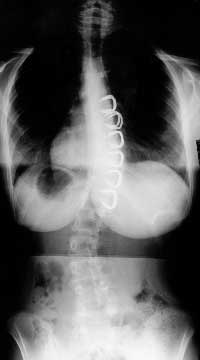

- So sieht eine Skoliose mit den Stapling (Klammern) in den WK aus.

- Stapling.jpeg (5.68 KiB) 8582 mal betrachtet

Die einzige Klammer-OP-Methode gegen Skoliose, die ich kenne, ist das an Shriner´s Children Hospital USA erfundene "Intervertebral-body-stapling"

Das sieht für Laien so aus als würden die Klammern an den Rippen ansetzen, aber sie werden IN DEN Wirbelkörper eingebracht und sollen den WK spreizen und das spiegelbildliche Gegenteil von Keilwirbeln bilden.